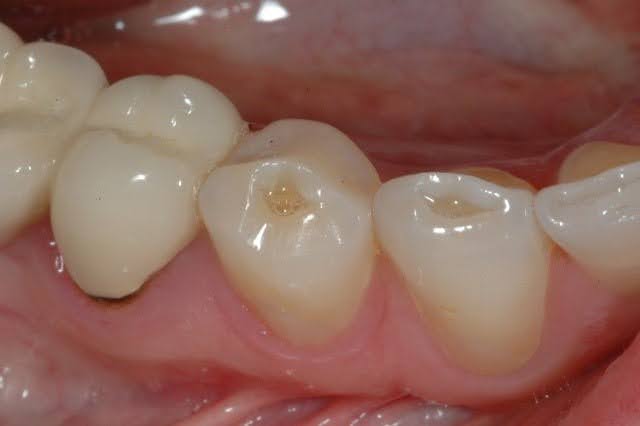

1. Tooth Decay (Cavities)

Cavities are one of the most common causes of tooth pain, especially when pressure is applied during chewing. As decay progresses, it weakens the outer enamel and exposes more sensitive inner layers of the tooth.

Cavities weaken the enamel and expose the inner layers of the tooth. When you chew, pressure hits these sensitive areas.

Signs:

- Sharp or localized pain

- Sensitivity to sweets or temperature

- Visible holes or discoloration

Treatment:

- Fillings (early stage)

- Crowns (advanced cases)